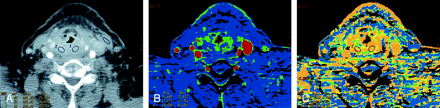

Patient 8 with atypical vascular proliferation of the vocal cord.

A, Contrast-enhanced neck CT scan shows a mass in the left true vocal cord. ROIs 9 and 11–13 are in the lesion, and ROI 10 is in the contralateral vocal cord.

B, CTP functional map shows a relatively low blood flow of 26–32 mL/100 g/min in the lesion in the left vocal cord. Right vocal cord has blood flow of 26 mL/100 g/min. Scale from red to blue corresponds to decreasing flow.

C, CTP functional map shows that the lesion has a relatively long MTT of 6.9–11.6 seconds. Scale from red to blue corresponds to increasing MTT.